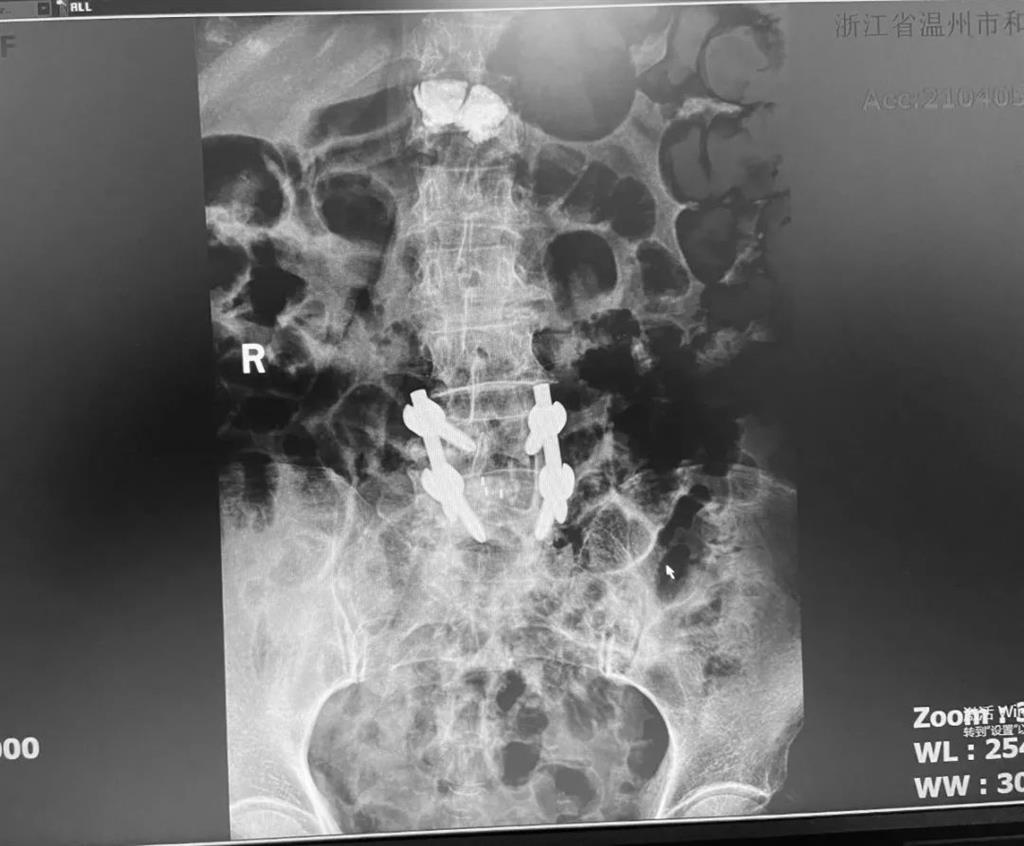

據了解,脊柱內鏡下腰椎融合術只需要打幾個“鑰匙孔”即可完成。聽起來是不是很簡單?在脊柱內鏡下,劉丹主任先后為患者進行了椎管減壓、椎間盤摘除,再實施椎弓根螺釘放置、椎體植骨融合內固定,一系列步驟有條不紊。

術中只需切開4個如“鑰匙孔”般大小的孔道